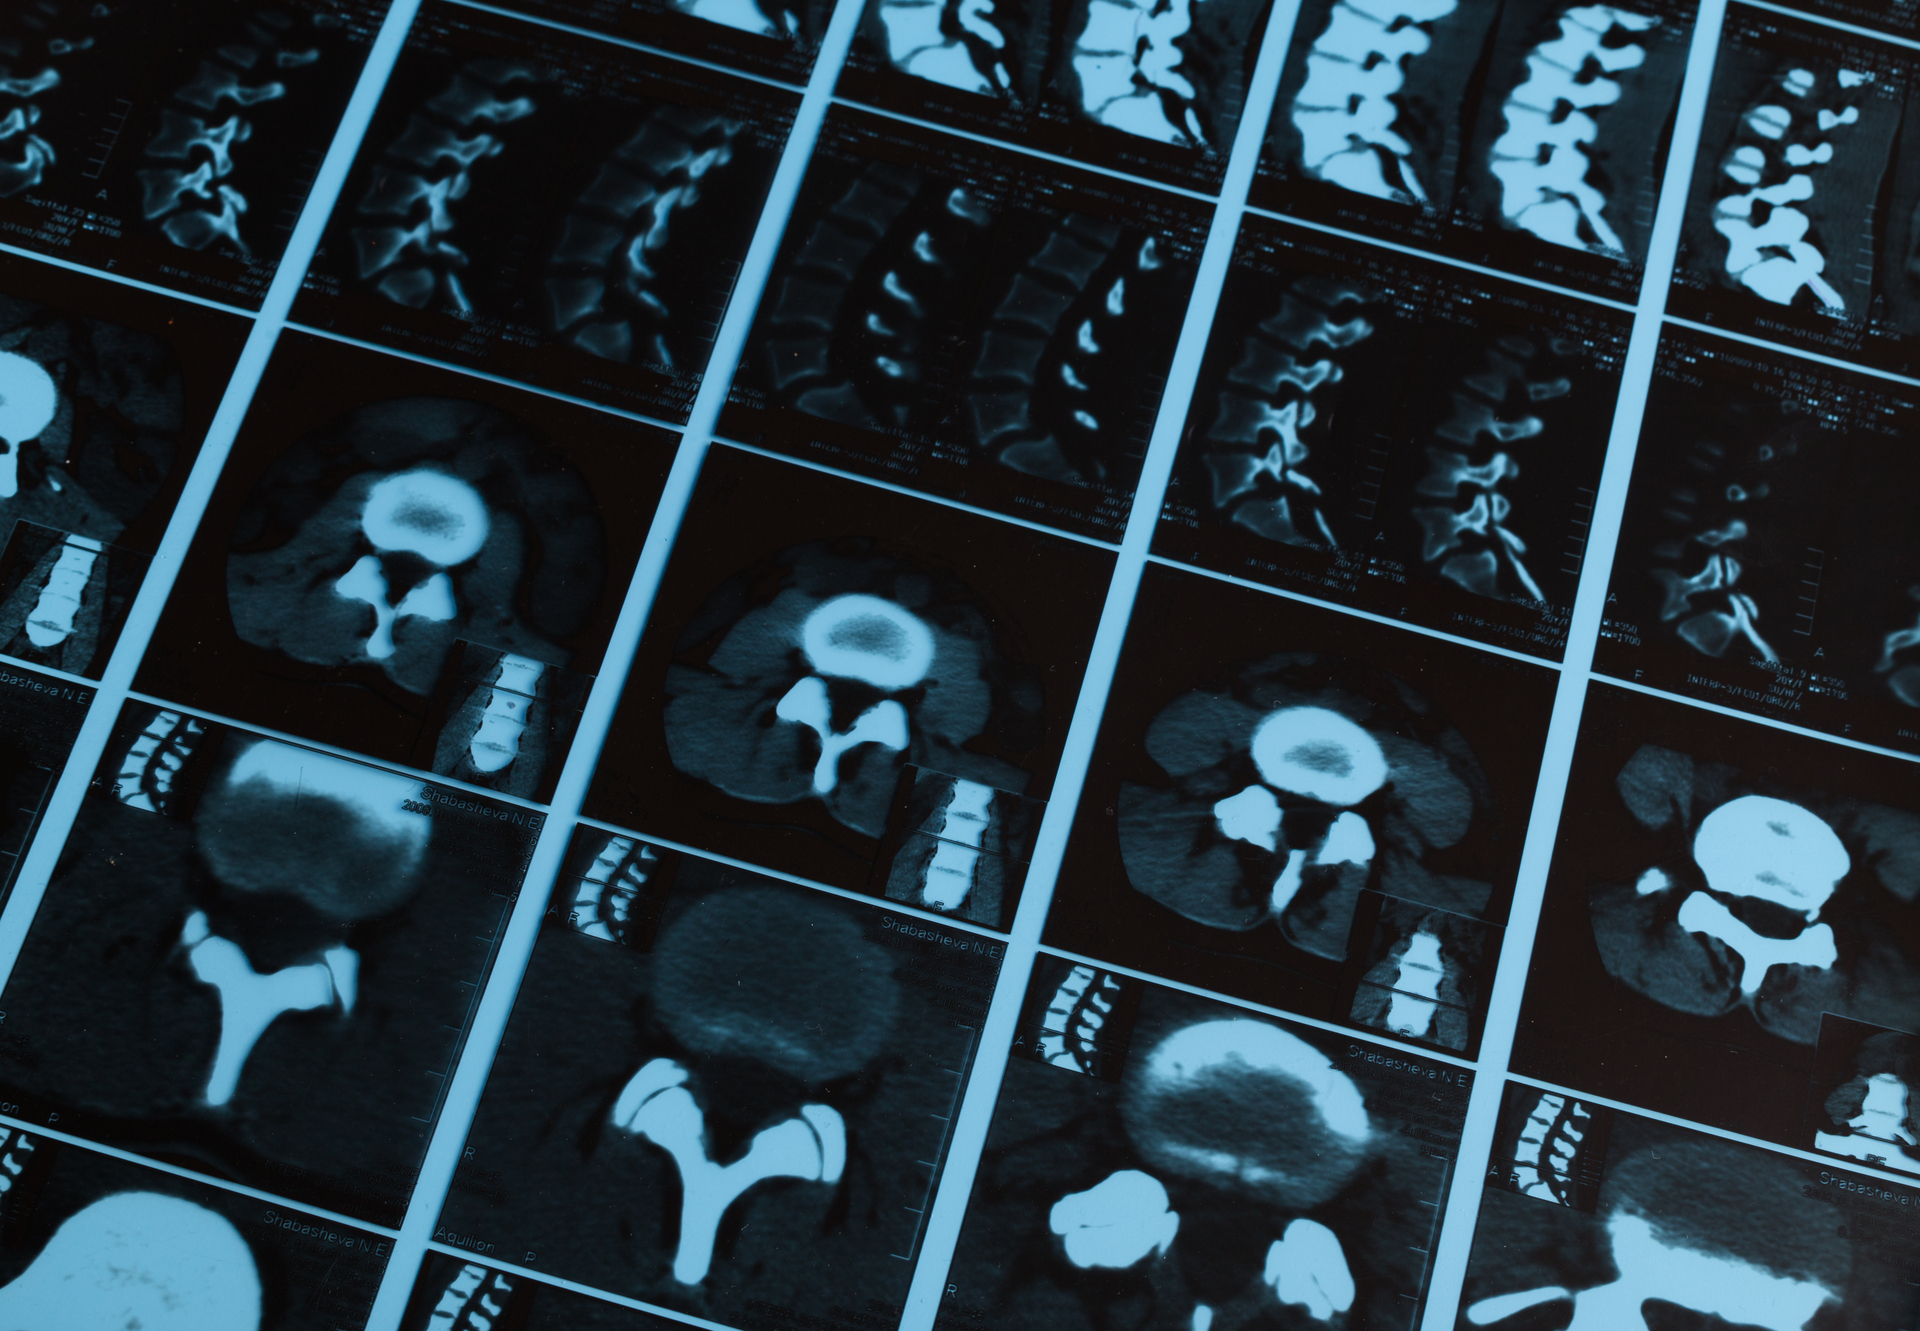

A whole spine MRI scan is a non-invasive imaging test that uses a powerful magnetic field, radio waves, and computer technology to create detailed images of your cervical (neck), thoracic (mid-back), and lumbar (lower back) spine. It allows clinicians to see the vertebrae, spinal cord, discs, nerves, and surrounding soft tissues in high detail.

A Spine MRI (Magnetic Resonance Imaging) uses powerful magnetic fields and radio waves to produce high resolution images of the cervical (neck), thoracic (mid-back) and lumbar (lower back) spine.

The scan clearly shows:

MRI is particularly useful for identifying conditions that may not be visible on X-rays or CT scans.